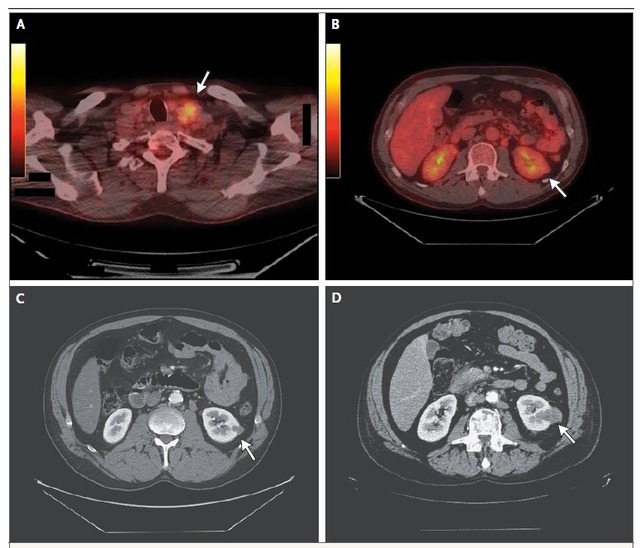

CT 扫描国家综合肿瘤中心和国家健康机构临床影像学指南推荐,在没有禁忌症的情况下,基线胸部、腹部、骨盆增强电脑断层扫描(CT)是原发灶不明的转移癌的检查标准。目前,表现为孤立腋窝淋巴结腺癌病变的妇女如果乳房 X 光和超声的检查结果均为阴性,应进行乳房磁共振成像(MRI)检查。MRI 检查没有发现乳腺肿块的患者乳房切除术发现肿瘤的概率极低。有创检查如纤支镜,胃镜,肠镜等仅适用于有临床症状且影像学和病理异常能够提示肿瘤来源的患者,无临床症状,临床和病理学未见异常的患者不适合使用有创检查以确定肿瘤来源。 PET-CT 检查肾功能不全或不能摄碘的患者可使用正电子发射断层造影(PET)-CT 或 MRI 检查。 目前 PET-CT 仅限于发生颈部鳞状细胞性淋巴结病变的不明来源的颈部肿瘤患者,PET-CT 有利于引导活检,确定病变范围,制定放疗计划以及监测疾病。这类患者也可以选择内镜检查(直接和间接喉镜,支气管镜和胃镜)和双侧扁桃体切除术。PET-CT 的作用尚不清楚,一些小型研究评价了 PET 在原发灶不明的转移癌患者中的应用。 Moller 等人回顾了18F- 氟代脱氧葡萄糖(FDG)PET 作为不明来源的颈外肿瘤患者检查手段的四项临床研究(共 152 例患者),这些研究在入选标准,研究设计以及使用 FDG-PET-CT 检查之前诊断检查手段方面存在异质性。FDG-PET-CT能够检测出 39%的不明来源的颈外肿瘤患者的原发部位。检测到的最常见的肿瘤原发部位是肺(约 50%的患者)。荟萃分析显示,FDG-PET-CT 在原发肿瘤原发部位检测方面的灵敏度,特异度和准确度分别为87%,88%和 88%。作者认为 FDG-PET-CT 在识别原发灶不明的颈外肿瘤的原发部位方面有一定的作用。虽然还没有前瞻性研究, PET-CT 扫描可以诊断出仅有单发转移病灶的肿瘤患者,并采用局部治疗,还可以作为主要累及骨的肿瘤患者的随访手段。图 2 显示 PET 扫描在评估小的原发肾癌方面还存在缺陷。

图 2 PET-CT 作为原发灶不明的转移癌的最初的检查手段存在缺陷患者男性,51 岁,有吸烟史,出现颈部淋巴结肿大。左锁骨上淋巴结活检发现转低分化癌。免疫组化染色显示细胞角蛋白(CK)7,CK20, 突触素,嗜铬粒蛋白,S-100,T 细胞识别的黑色素瘤抗原(MART-1),前列腺特异性抗原,甲状腺转录因子 1(TTF1),抑制素,和甲状腺球蛋白均为阴性,PAR-1,CD10, 和低分子量的角蛋白呈阴性,病理结果无特异性。基线头颈部 PET-CT 扫描发现颈部多个高代谢结节(图 A,箭头)。PET-CT 检查并没有发现肾脏原发癌,回顾性研究则发现肾脏有一小病灶(图 B,箭头)。肾癌倾向的原发灶不明的转移癌患者给予紫杉醇和卡铂化疗。化疗后病人疾病轻度进展。患者进行组织来源分子分析提示肾癌来源。淋巴组织肾特异性免疫组化检测表明,PAX-8, CD10,上皮细胞膜抗原,和波形蛋白阳性 - 结果与普通转移性肾细胞癌一致。增强 CT 扫描发现左肾下极有一个肿块(1.0~1.2 CM) (图 C,箭头)。患者随后给予靶向治疗药物,包括依维莫司, 阿西替尼,帕唑帕尼。最初患者获得部分缓解,随后疾病进展,累及淋巴结,肝,骨和肾(图 D,箭头)。该病人没有诊断为原发灶不明的转移癌,而是转移性肾细胞癌。然而,即使诊断正确,大多数晚期肾癌患者的疗效较差。